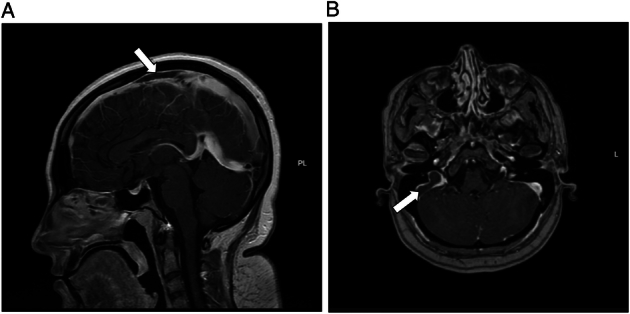

Case report: This case report describes a young woman with CVST who did not respond to low-molecular-weight heparin (LMWH). The patient was initially treated with LMWH; however, her symptoms and clot burden in the sagittal sinus worsened, and coagulation studies showed no evidence of therapeutic anticoagulation despite good compliance. Unfractionated heparin was then initiated, and the patient's symptoms improved dramatically within 24 hours, along with the recanalization of the cerebral venous sinuses. Genetic testing revealed a heterozygous mutation in the prothrombin gene (G20210A). This mutation is a known risk factor for CVST. However, it is unclear why the patient did not respond to LMWH but responded appropriately to unfractionated heparin.

Abstract Image